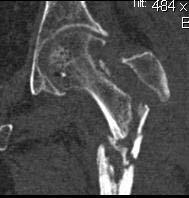

If there is no osteomyelitis, I would recommend open insertion of Gamma Nail

and Bone Grafting.

кт